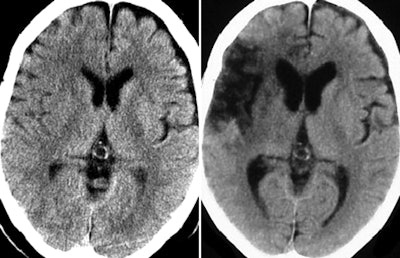

| Perfusion maps generated from identical source data by using different software. Unenhanced CT images (above) and perfusion maps (below) in 73-year-old man with right middle cerebral artery occlusion. CBF, CBV, and MTT/TTP maps generated with all software and by using sSVD and bSVD methods are displayed with same color lookup table, automatic color scale determination, and vascular pixel elimination. On unenhanced scan at admission (above, left), faint hypodense areas in right frontal operculum and basal ganglia are noted and final infarct area is identified on follow-up unenhanced scan (above, right). Decrease in CBF area measured with sSVD is much larger than that measured with bSVD, which is comparable with final infarct area. Software A, C, and E show almost same CBF changes as sSVD, while software B and D show almost same changes as bSVD. Abnormal MTT/TTP areas in sSVD and software A, C, D, and E were apparently larger than those in bSVD, software B, and final infarct area. Note that an erroneous MTT/TTP decrease in software A, B, D, and bSVD is seen in area of significant CBV decrease. Areas with CBV decrease are almost the same among all software. All images republished with permission of the Radiological Society of North America from Radiology, January 2010, Vol. 254:1, pp. 200-209. |